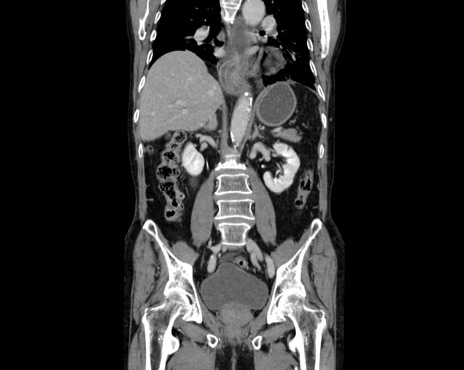

症例26(冠状断像)

【症例】80歳代男性

【主訴】嘔吐

【現病歴】昨晩2回嘔吐あり、今朝になっても嘔吐あり。来院。

【既往歴】胃潰瘍

【身体所見】意識清明、BT 37.6℃、BP 166/95mmHg、HR 100bpm、SpO2 97%、腹部:平坦・軟、腸蠕動音聴取良好、圧痛なし。

【データ】WBC 21900、CRP 1.4